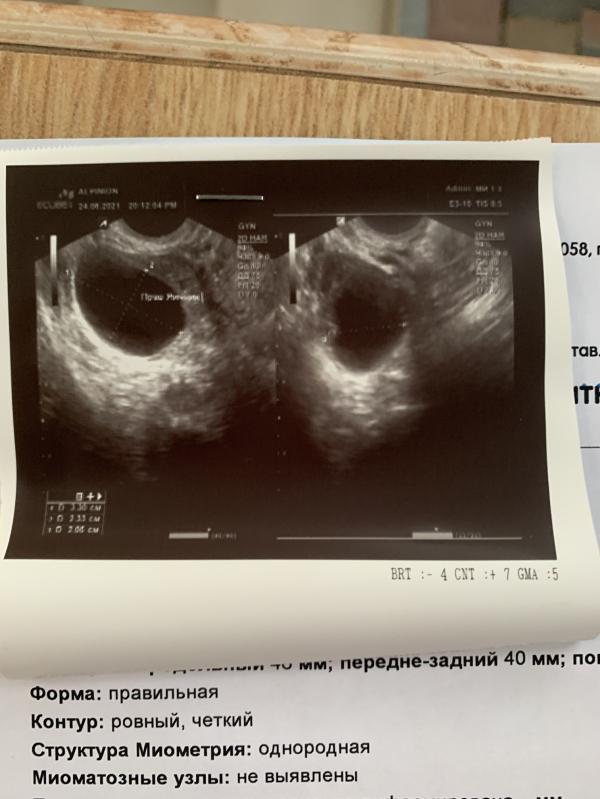

Уже 3 см в размере набрала. Ужас.

И сейчас я вновь столкнулась с этой гадостью, пока не болит, но ощущение вздутости постоянно. Беременность исключили, тк овуляции не было и матка норм размеров. Лечение до сих пор не назначили, тк ближайшая запись ко врачу в жк аж на 19 июля.

Фолликулярная

Сказали, что сама рассосётся

Вот только надо курс таблеток пропить